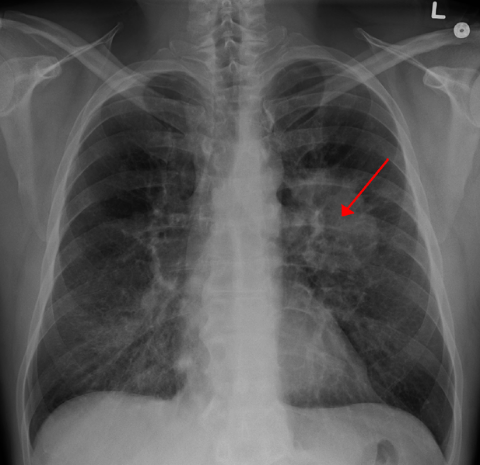

根据今天在 Cell 发表的新的西奈山研究报告,在晚期肺癌患者中取得显著效果的免疫治疗也可能对新诊断的患者抱有很大的...